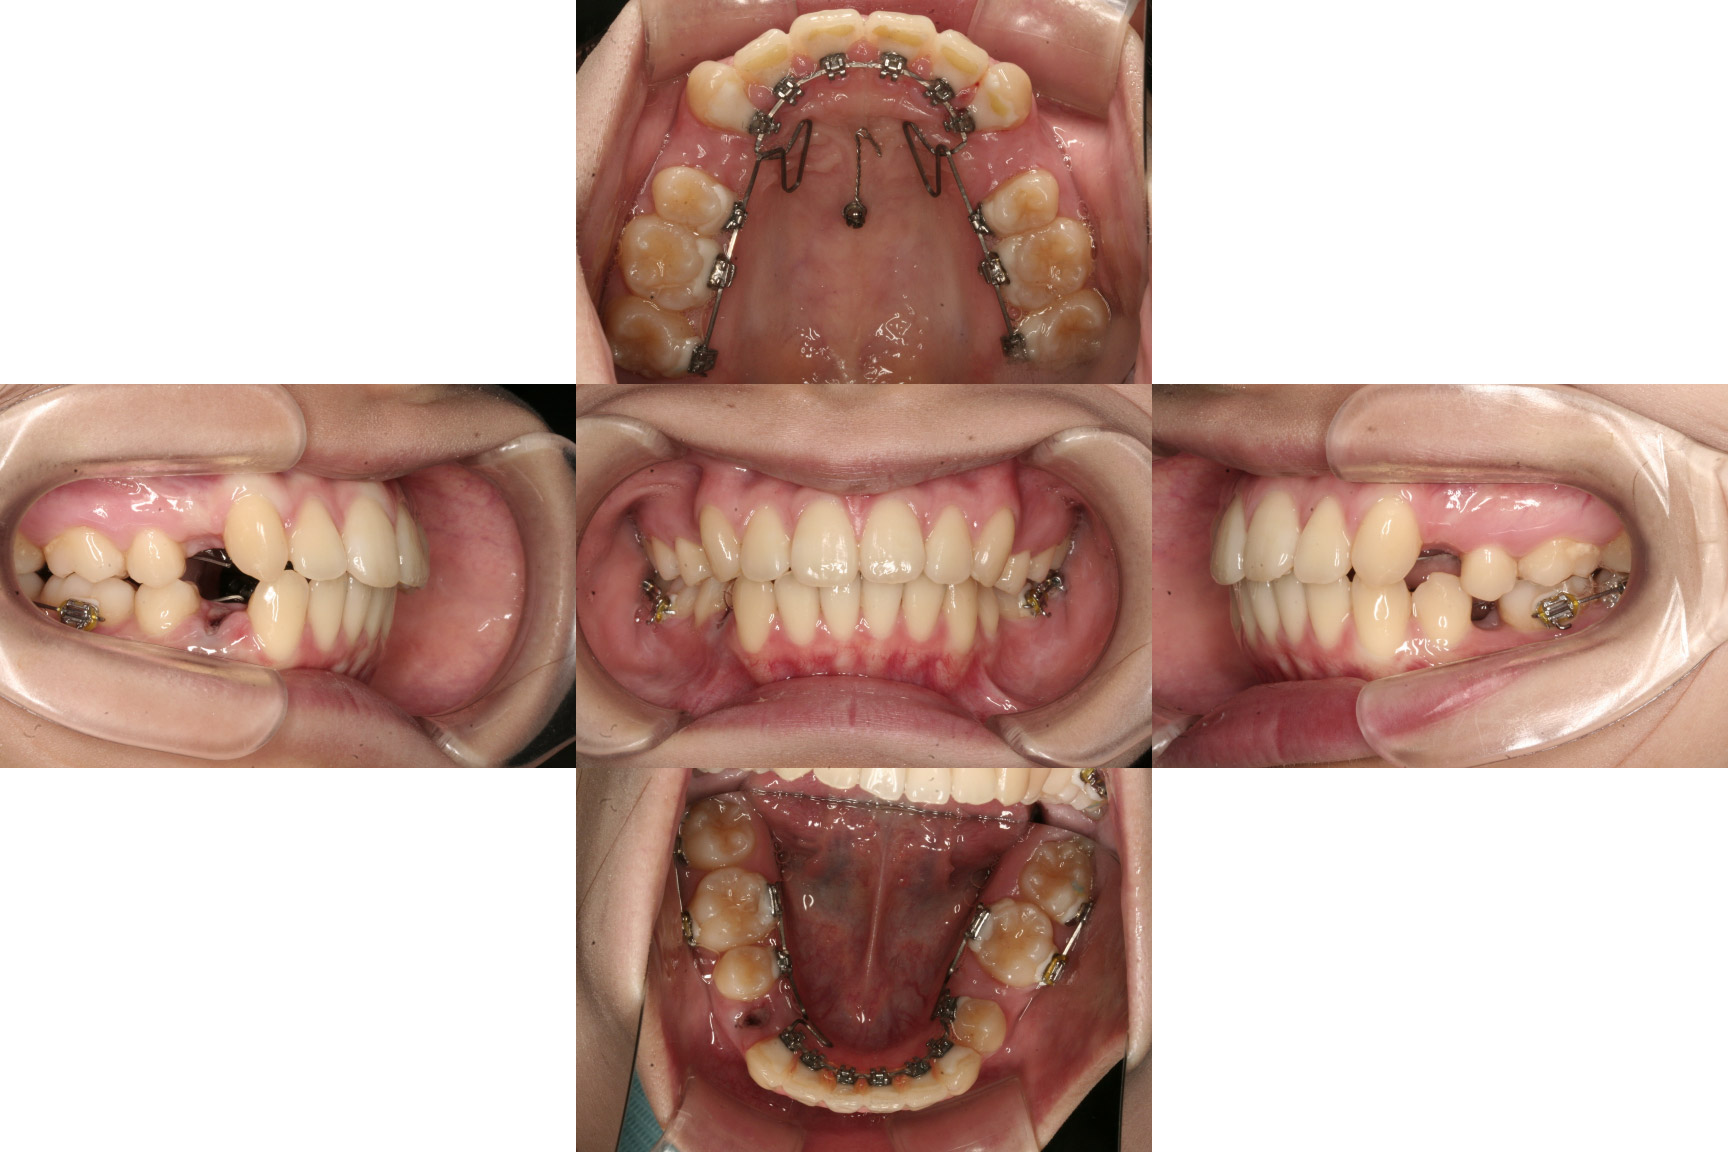

装置装着後